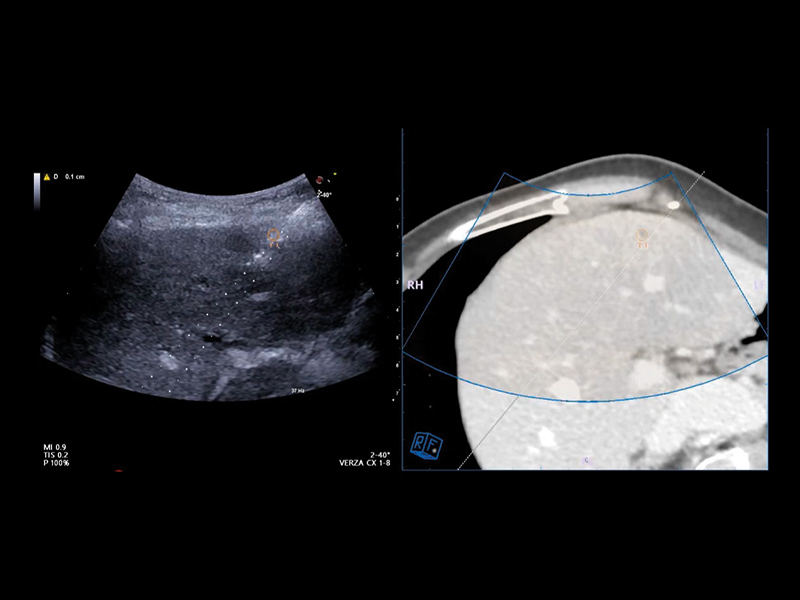

Virtual Navigator (VNav), as the most advanced Esaote Fusion Imaging technology supported by Artificial Intelligence, is opening new horizons in cross-modality liver imaging. Virtual Navigator provides a very simple and active coupling of ultrasound examination with a second Dicom modality imaging (MRI/CT/Pet-CT) dataset as a reference. It enables real-time navigation to benefit from both modalities to increase confidence and accuracy throughout interventional procedures on the liver.

Virtual Navigator will bring you particular support when you face complicated liver pathologies or conditions during your procedures, particularly in the following cases:

• Lesions which are better identified with CT, MRI, and PET or slightly visible in US

• Lesions which are only visible during arterial phase enhancement

• Follow-up of local tumours after ablation or resection

• New lesions in subsequent follow-up surgery or ablation.

• Hidden lesions during treatments (gassed out US).

• Composite ablations requiring multiple needle insertions.

• Complex geometries or difficult treatment planes to identify a safe pathway to the target, such as a difficult US “window”, or complex angle of insertion.